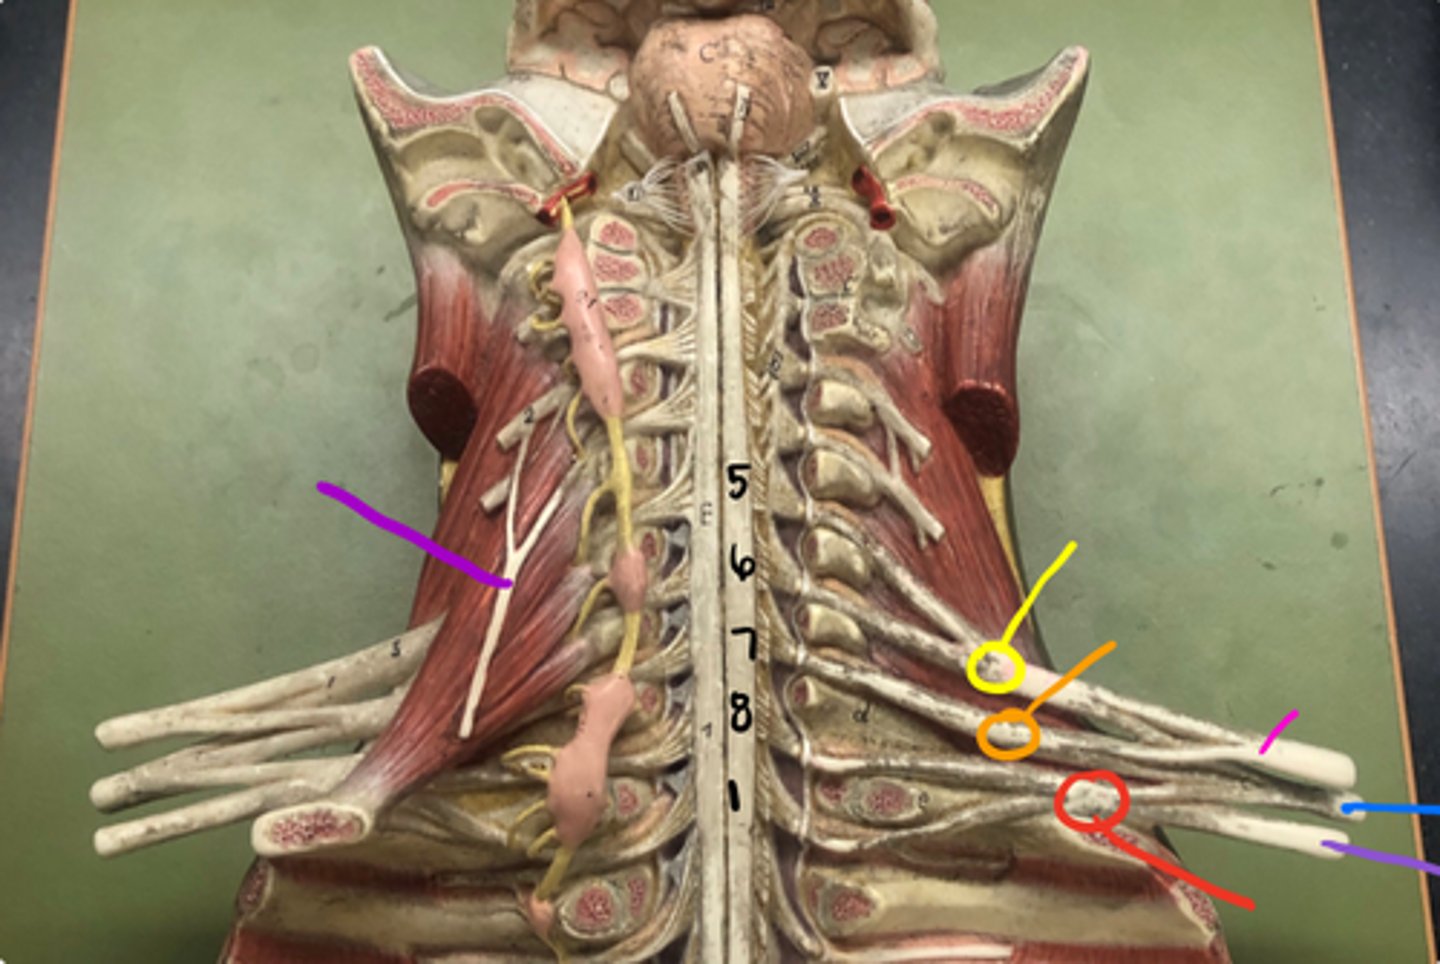

phrenic nerve

neon purple (on neck)

superior trunk

yellow

middle trunk

orange

inferior trunk

red

lateral cord

pink

medial cord

purple

posterior cord

blue